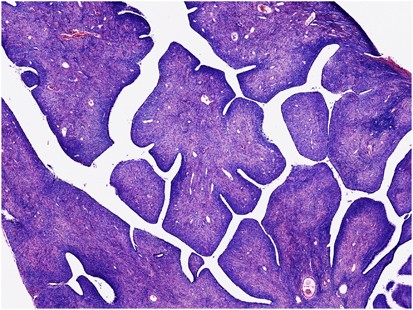

Histologically, the mixed nature of the tumour is exemplified by the presence of both epithelial and stromal elements, the latter predominating. At low power magnification, the tumour often has a phyllodes-like (leaf-like or club-like) architecture (Figure 7). The epithelial elements usually consist of glands, which may be dilated or slit-like with a phyllodes-like appearance, lined by cuboidal or low columnar cells. In most cases, the epithelium is endometrioid and resembles proliferative endometrium, although ciliated, mucinous and squamous epithelium may also be seen. Uncommonly, the epithelial component exhibits glandular complexity resembling atypical hyperplasia/endometrial intraepithelial neoplasia or carcinoma. The latter is usually a low-grade endometrioid carcinoma.28 The stromal component, which is typically low grade, is composed of spindled and/or round cells with scant cytoplasm, but rarely can be high grade. Intraglandular protrusions of stroma and the manner in which the stromal cells, which often resemble endometrial stromal cells, concentrate around or beneath the glandular elements (‘periglandular cuffing’) are characteristic (Figure 8). The ‘cuffing’ may be very thin (and thus overlooked) but is where nuclear atypia and mitotic activity are typically found (Figure 9). Although a mitotic rate of ≥2 per 10 high power fields (HPFs) is often seen, some tumours have a lower mitotic rate and should be diagnosed as adenosarcoma if the tumour has the characteristic aforementioned features as reflected in the 2014 WHO classification.1